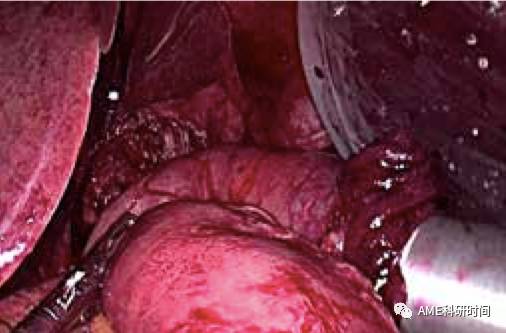

3 检查无活动性出血、冲洗术野后,脾窝及肝下各留置引流管 1 条,撤离腹腔镜器械、放气,术毕 ( 如图 49-50)。

图49 肝下引流管

图50 脾窝引流管